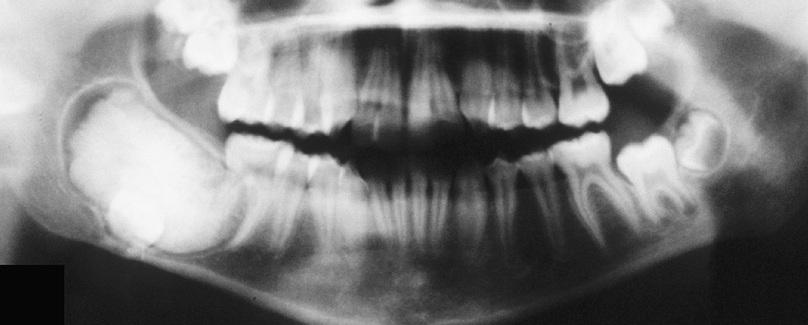

Large cysts present in the right and left mandibular molar regions, together with a smaller cyst involving the right maxillary canine.

nevoid basal cell carcinoma syndrome